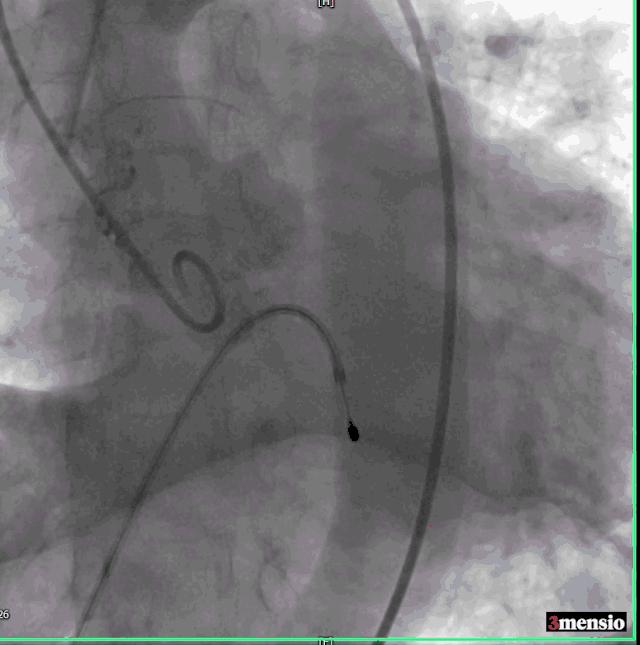

右侧股动脉鞘经Amplatz Super Stiff导丝引导更换为14F 导引鞘,经右侧股动脉用直头导丝带AL2造影管至升主动脉,在直头导丝引导下成功跨越主动脉瓣。

交换Amplatz Super Stiff导丝,再送猪尾导管至左心室,测量左室压力142/6mmHg,升主动脉压力254/58mmHg,跨瓣压差112mmHg,交换Amplatz Super Stiff导丝至左室,撤出猪尾导管,在临时起搏器控制性降压下用20mm球囊扩张主动脉瓣。

球囊扩张